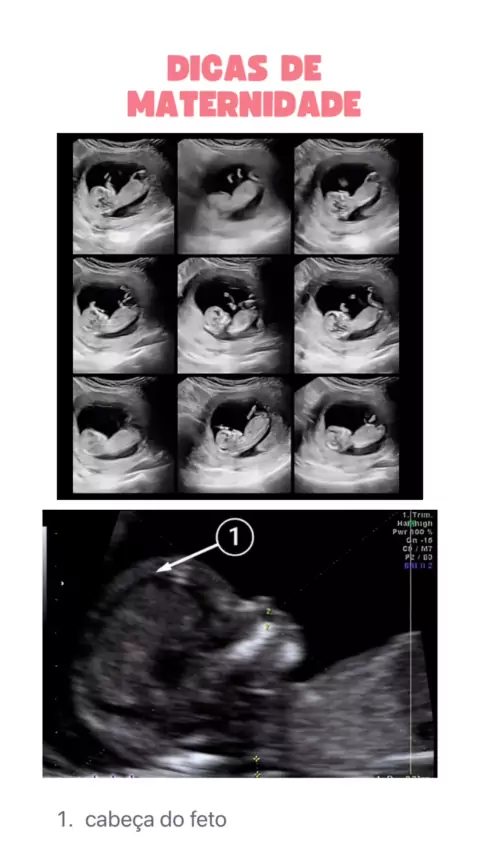

Maternidade - De mãe para mãe

#EstrelaDeFamília #sinoestas #ultrassom #ultrassommorfologico #👶🏻bebe